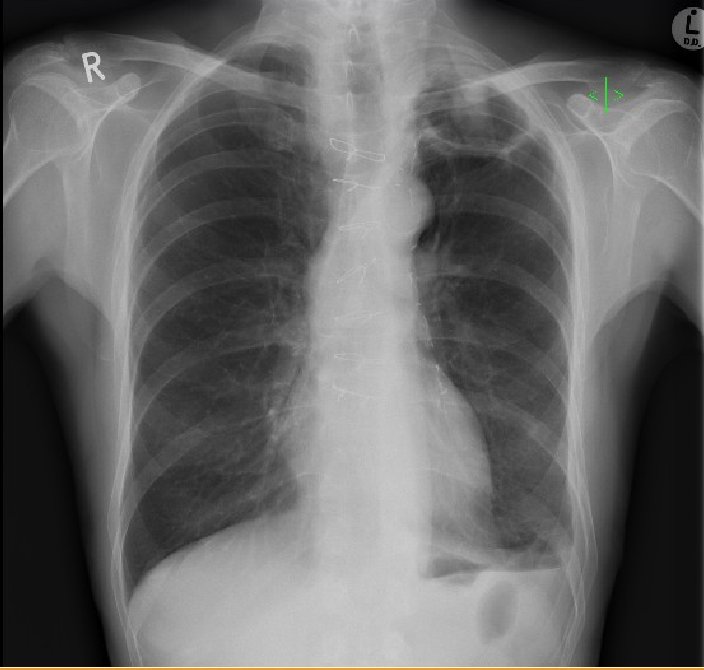

Figure 4. Air-fluid level in apical cavity with adjacent upper-lobe consolidation.

The consolidation surrounding the cavity on CT and the new tree-in-bud opacification are suggestive of pulmonary infection, be it bacterial or fungal. This upper-lobe consolidation is also apparent on the plain chest radiograph, as is an air-fluid level. The above findings would be consistent with bacterial pneumonia, and the presence of an aspergilloma-containing cavity increases the susceptibility to bacterial infection. The clinical picture would also be consistent with a bacterial superinfection – cough productive of green sputum, upper-lobe crackles on auscultation and raised white cell count with associated neutrophilia. Diagnosis would be based on a positive bacterial culture on sputum or bronchoalveolar lavage specimens, and clinical and radiological improvement with appropriate antibiotic treatment.